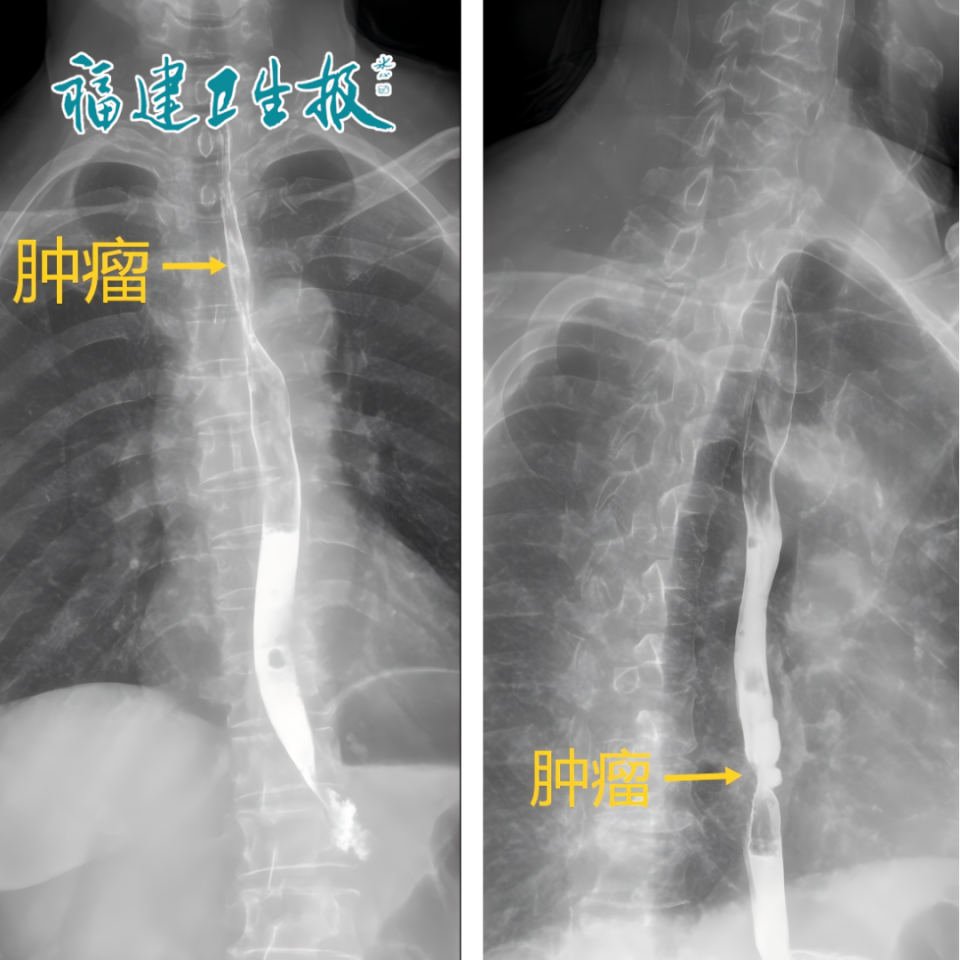

可谁也没想到,在做胃肠镜的时候,夫妻俩都被查出了食管癌幸运的是夫妻俩发现及时,没有转移,尚属于早期。

▲夫妻俩都发现食管癌